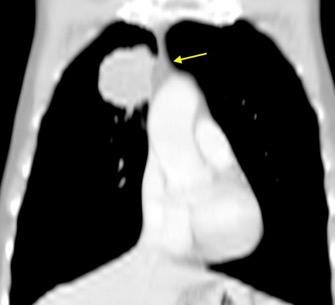

De los pacientes con Tumor de Pancoast

1,7% tienen una radiografía de tórax normal

Fletcher F et al. The normal chest radiograph in bronchial carcinoma. Br Med J. 1976

Hallazgos en TC de invasión local Fiabilidad diagnóstica: 62,7-72,3%.

Valor predictivo positivo: 41,1%-56,4%.

La predicción basada en TC es un falso positivo en casi 50% de los casos